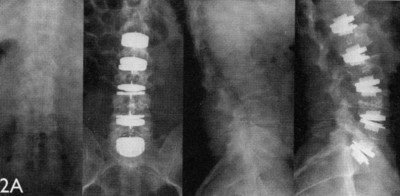

The LaserCUSING additive laser melting method combines the strengths – and eliminates the weaknesses – of traditional titanium or PEEK components for spine cage applications. A laser-melted component can now offer the biocompatibility of titanium with the desired elasticity of a plastic material in a single product. Laser-melted spine cages have a very complicate geometry and not require to be re-treated (images 1a, b and c) to ensure an optimal surface structure. The highlight of this solution: its geometry, with partially different density distributions (embedded web-like structures), now gives titanium parts the same elasticity as a PEEK solution. Laser-melted cages can also be affordably manufactured in various dimensions depending on the anatomy of the patient, allowing for customised manufacturing. According to CEO Stefano Caselli, laser-melted cages represent "a true innovation that combines material-specific advantages such as biocompatibility, i.e., the ability to embed the material into the bone structure, and elasticity that is customised for the human body in a single product" (image 2). Surgeons can easily locate the cages using CT or MRI imaging. Laser melting also allows custom or small-series manufacturing, including "made-to-order" cages for patients with special anatomical conditions or standard solutions for other patients. A clinical study conducted in March 2014 in cooperation with Carl von Ossietzky University in Oldenburg, Germany, confirmed an excellent healing prognosis with these implants. (*Oldenburg study)